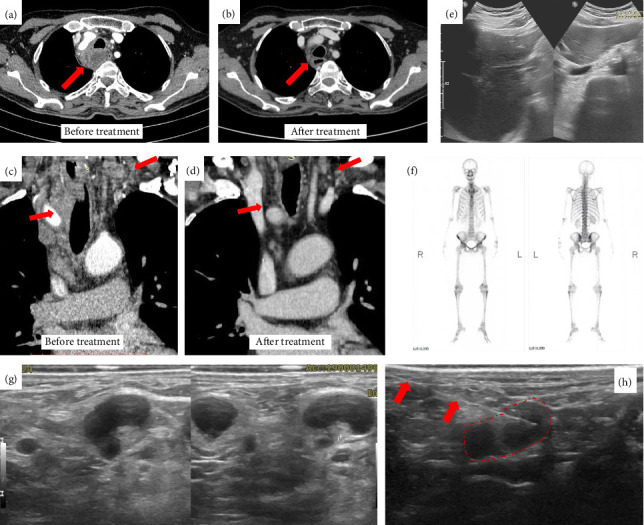

Necrotizing sarcoid granulomatosis (NSG) is a rare disease characterized by granulomatous and necrotic features as well as vasculitis, and it primarily affects the lungs, with occasional extrapulmonary manifestations. The first documented case was in Jakarta, Indonesia. A 71-year-old male presented with prolonged fever, a neck mass, and multiple mediastinal lymphadenopathy. The disease was initially suspected as lung tuberculosis, but a surgical biopsy of the left thyroid lobe confirmed the NSG pattern. Treatment with oral prednisolone led to positive outcomes, as evidenced by radiological improvement at the 3-month follow-up. This case report aims to emphasize the challenges and the importance of clinician awareness in diagnosing NSG.